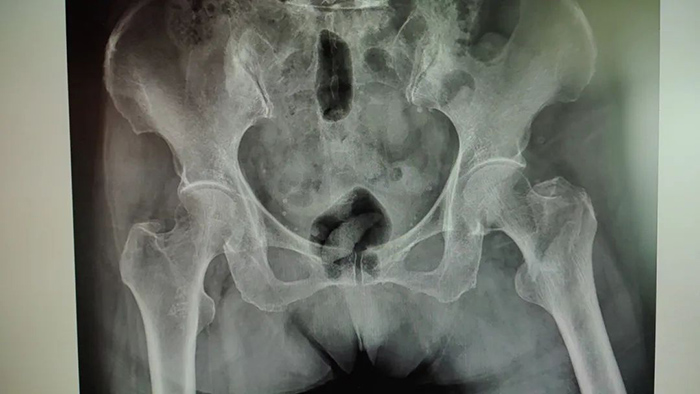

患者术前影像

今年93岁高龄的叶老太在家中不慎跌倒,导致左股骨粗隆间粉碎性骨折,家人赶紧将其送往51黑料

中医骨伤科。

入院时,叶老太脸色苍白,精神状态极差,血红蛋白浓度只有60g/L,且伴有高血压、冠心病、糖尿病等多种慢性疾病,如果长期卧床,会出现肺部感染、尿路感染等并发症,甚至危及生命!